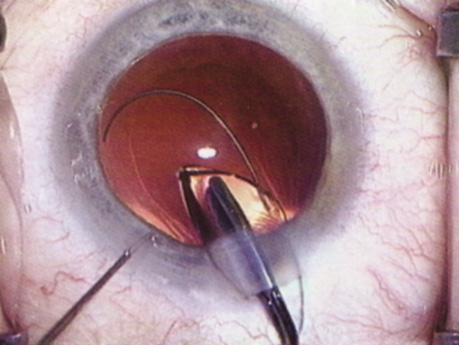

Hydrodissection can be performed after the surgeon has successfully completed capsulorrhexis.97 If the capsulorrhexis is not intact, fluid forced around the interior of the capsule may cause the bag to splay open. With capsulorrhexis, hydrodissection is a safe and extremely useful maneuver. Hydrodissection can be thought of as two maneuvers: hydrodelineation and cortical cleaving hydrodissection. By placing a 27-gauge cannula on a syringe filled with balanced saline solution (BSS), the surgeon can direct fluid beneath the residual anterior capsular rim to create a cleavage plane. Depending on the direction the fluid wave takes, different lamellae of the cataract will be separated. Hydrodelineation is the term used when the cleavage plane separates the adult nucleus from the fetal nucleus or the adult nucleus from the more peripheral epinucleus. Hydrodelineation often results in the characteristic golden ring sign (Fig. 11). Cortical cleavage occurs when the cortex is separated from the capsular bag (Fig. 12). Finding the cortical cleavage plane may be facilitated by gently lifting the capsular margin away from the cortex with the BSS cannula before injecting. Several small bursts of fluid allow the surgeon to monitor progress of the fluid wave. When dealing with a soft nucleus, the authors strive to perform true cortical cleaving hydrodissection. For a hard nucleus, hydrodelineation allows manipulation of less of the nuclear bulk, although the remaining epinuclear shell must be addressed in an additional step. Hydrodelineation is particularly useful if the nucleus is not freely mobile after cortical cleaving hydrodissection.

Fig. 11. A crisp “golden ring” is seen from the fluid cleft between the epinucleus and nucleus with hydrodelineation.

Fig. 12. Hydrodissection, performed subincisionally with a 27-gauge J-cannula, produces a cleavage plane between the capsule and the cortex. The small blue arrows indicate the advancing fluid wave.